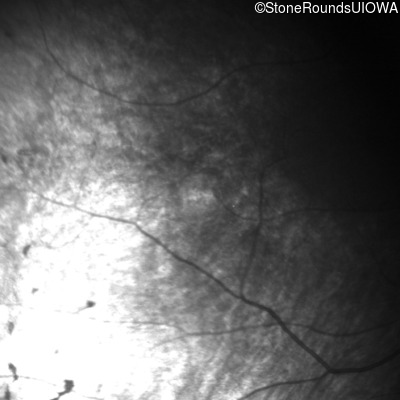

Infrared Fundus Photograph - Right - Light Perception

Exemplar